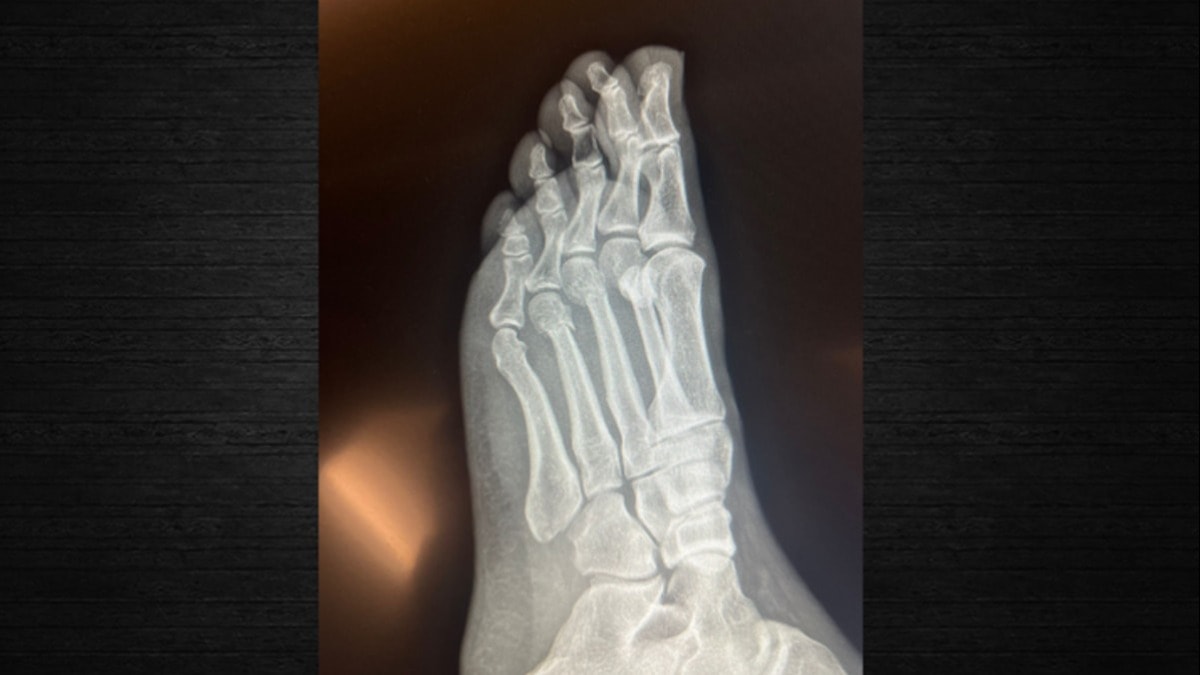

‘Parmak kemiklerinde kırıklar var’

CHP Genel Başkanı Özgür Özel’in “Herkes inceleyebilir” dediği filmleri SÖZCÜ, Ortopedist Prof.Dr. Tarık Yazar’a incelettirdi.

Prof. Yazar, Özgür Özel’e ait elimizdeki röntgen filmlerini inceleyerek şunları söyledi: “Sayın Özgür Özel’in röntgen filmlerini incelediğimizde parmak kemiklerindeki kırıkları gördüm. Açık bir yara olmaması bir şanstır. Yani, dışarıya kan akmamış. Röntgende yara olup olmadığı her zaman görülmez. Ancak, Özgür Bey’in röntgenini incelediğimizde yine de şanslı olduğunu gördüm. Biz buna ‘şanslı kırık’ deriz. Aslında tam kırık da diyemeyiz. Ayrılmamış, kemiğin özelliği bozulmamış. İyileşme yeteneğinin fazla olduğu bir bölgede kırık var. Şanslı tarafı kanlanmanın kuvvetli olduğu bir bölgede kırık gördüm. Bilgisayarlı tomografiyle takibi uygun olur. Tedaviye doğru başlanmış. Mutlaka iyileşecektir. Kullandığı ayak desteği gayet doğru bir seçim. Üç aya kalmaz tam iyileşme gerçekleşir. Lütfen bir daha düşmesin.”